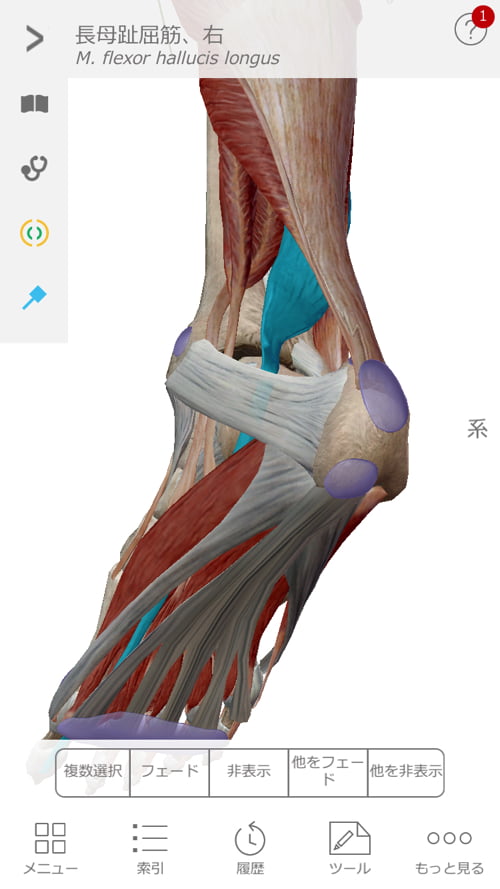

施術はまず足首から足の甲、そして膝へ繋がるこれらの筋肉や腱を調え直しました。

図で分かるように足の甲から膝へ、足裏から膝へと繋がっています。

そして膝から上は腰骨に繋がっているので、膝は足首にも腰にも影響があるのです。

足の裏はかなりヨジレもあり張っていました。

ズバリ足首の痛みの原因はこの足裏のヨジレ。

そして足裏の不調が膝を歪め、腰に痛みを生み出しています。